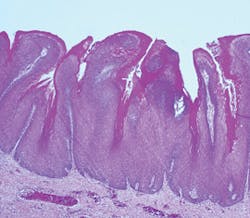

Verrucous carcinoma is a progressive type of lesion, developing from a smooth appearance to clinically varying appearances of white, cauliflower-like and papillary forms. Verrucous hyperplasia and verrucous keratosis may be clinically indistinguishable from verrucous carcinoma at various stages (Alkan et al., 2010). They may coexist and be both clinically or microscopically undifferentiated in varying stages.

Clinical characteristics: Early lesions may be more subtle, appearing as flat white-light pink lesions and described as simply "leukoplakia" when viewed clinically. Clinical descriptions may include terms such as sessile, smooth, and spreading over an extended area of tissue. Some fissuring and ulceration may occur at times. As the lesions increase in size, descriptors such as exophytic, verrucous-like with keratosis, or warty may be used to note the lesion. Leukoplakia may be considered a more serious type of lesion when progression is observed and may ultimately be further classified as verrucous carcinoma. A biopsy is always needed for confirmation.

Pathogenesis: Verrucous carcinoma is thought to be a verrucous variant of squamous cell carcinoma. As lesions progress over time, they become verrucous carcinoma. The entity "verrucous hyperplasia" was designated as a precursor to verrucous carcinoma, squamous cell carcinoma, and papillary squamous carcinoma. Van der Waal (2008) suggests that verrucous hyperplasia and perhaps verrucous carcinoma are probably underdiagnosed histopathologically, and may be reported as benign verrucous or papillary proliferations without signs of epithelial dysplasia or invasive growth.